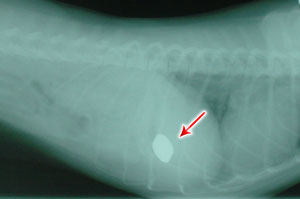

RoxySome cats will eat anything they can get down their throat. Most of the time, it's harmless items that get digested, or are small enough to go through the digestive system without harming the animal, but on rare occasions we do see strange X-Rays like ROXY's who had ingested 4 pennies (not the best way to save!). Fortunately Roxy is healthy and doing well now. She has since kept herself away from money, wich gives her owner Melissa more money to spend on Quality food.